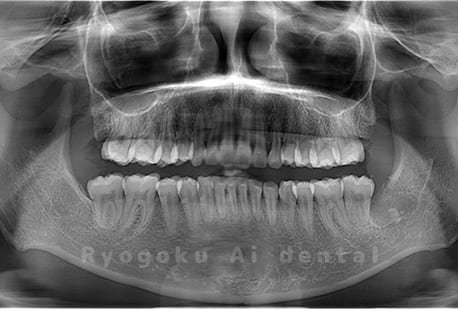

水平埋伏の親知らず

歯茎の中で完全に横に生えてしまうタイプです。

この親知らずを水平埋伏智歯と言います。このタイプはほとんどが下顎のケースです。真横に生えているので抜歯の際は難易度が高く2~3つに砕いて分けて抜歯をします。